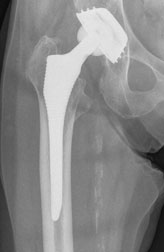

Nach Ausschöpfung aller konservativen Maßnahmen ist die operative Therapie bei einer röntgenologisch nachgewiesenen Coxarthrose mit erheblicher funktioneller Beeinträchtigung, sowie Beschwerden im Alltag und Beruf indiziert. Dabei werden normalerweise sowohl der Hüftkopf, als auch die Hüftpfanne ersetzt, man spricht daher von einer Totalendoprothese (TEP). Die Prothese kann dabei im Knochen durch Knochenzement verankert oder durch eine spezielle Oberflächenbeschichtung zementfrei fixiert sein. Von einer Hybrid-Implantationstechnik spricht man, wenn der Schaft einzementiert und die Pfanne zementfrei eingebaut wird.

Prothesen Hüfte: Prothese zementfrei / Prothese zementiert

Zementierte Prothese

Hybrid Prothese